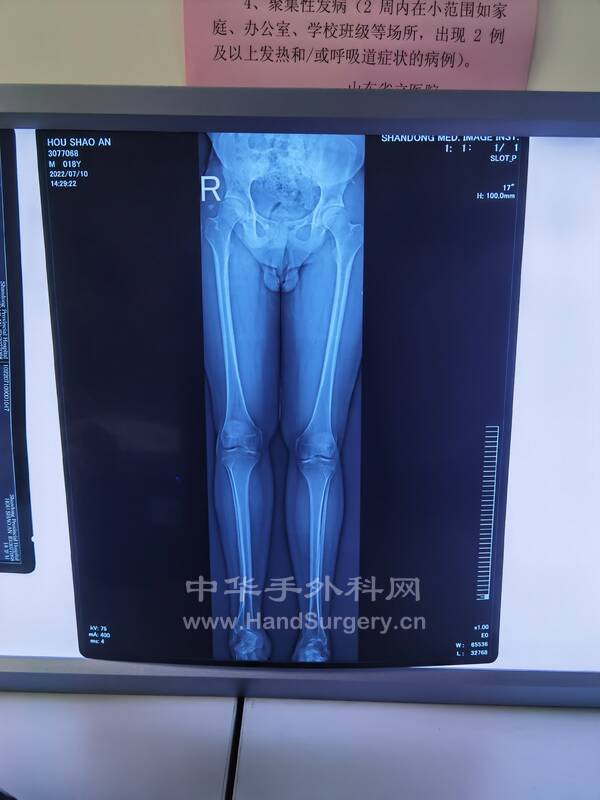

2.三代遗传的马蹄足患者,今日手术(见图),术式:经皮跟腱延长术,跖筋膜松解术,胫前肌腱1/2转位术,跟骨截骨外移术,第一跖骨上抬术,组合式外固定架固定术

马蹄内翻足患者DR片:

双足正侧位(负重位),双踝正侧位(负重位),双下肢全长正位,双跟骨轴位